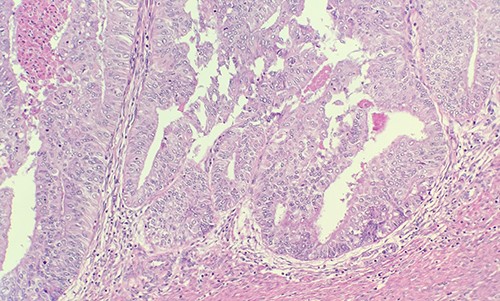

Patient was admitted for hysterectomy for endometrial carcinoma. There is a mass lesion measuring 4.3 × 4 cm located in right ovary indicating metastatic from uterine endometrial primary on image study. Microscopic examination of endometrial reveals endometrial adenocarcinoma, endometrioid type, FIGO Grade 2 (Fig. 1). Microscopic examination of ovary shows solid growth of tumor cells with angulated pale nuclei and nuclei grooves (Fig. 2). Tumor cells are positive for CD56, CD99, Calretinin (Fig. 3) and inhibin, combined with morphological features; this immunoprofile supports the diagnosis of granulosa cell tumor, adult type.

Tumor cells are positive for Calretinin by immunohistochemical stain (IHC ×40).